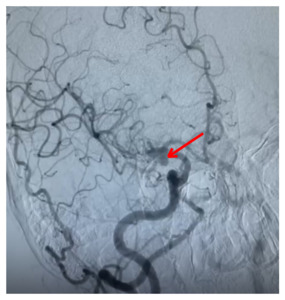

Computed tomography angiography (CTA) revealed an anomalous saccular aneurysm (7×5 mm) arising from the M1 segment of the right middle cerebral artery [Figure 2]. This finding was unusual as the branching artery demonstrated characteristics consistent with orbitofrontal artery territory supply. Digital subtraction angiography (DSA) performed via right femoral approach using a JR 3.5 5F guide catheter confirmed a Type 3 aortic arch with the anomalous aneurysm location [Figure 3]. The aneurysm demonstrated a broad neck and favorable morphology for microsurgical intervention.